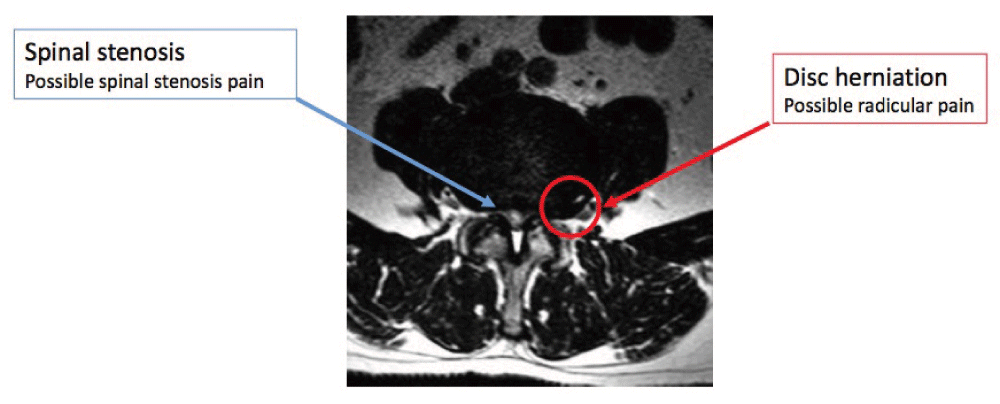

Radicular pain is pain evoked by ectopic discharges emanating from an inflamed or lesioned dorsal root or its ganglion; generally, the pain radiates from the back and buttock into the leg in a dermatomal distribution44. Disc herniation is the most common cause, and inflammation of the affected nerve rather than its compression is the most common pathophysiological process. Radicular pain is pain irradiated along the nerve root without neurological impairment. Even though it is nociceptive pain, it is distinguished from usual nociception because in radicular pain the axons are not stimulated along their course or in their peripheral terminals but from the perinevrium40,46. Radicular pain differs from radiculopathy in several aspects. Radiculopathy is a neurological state in which conduction is impaired along a spinal nerve or its roots. When sensory fibers are impaired, numbness is the main symptom and sign, whereas when motor fibers are blocked weakness ensues. Diminished reflexes can occur as a result of either sensory or motor block. The numbness is dermatomal in distribution and the weakness is myotomal. Although radiculopathy and radicular pain often accompany one another, radiculopathy has been observed in the absence of pain, and radicular pain may happen in the absence of radiculopathy46,47. It is important to underline that, contrary to popular belief, it is not possible to make a distinction among the patterns of L4, L5, and S1 radicular pain48,49. In fact, only when radiculopathy is seen together with radicular pain can segments be estimated. In such cases, the dermatomal distribution of numbness indicates the segment of origin rather than the distribution of pain. Lumbar disc herniation with radiculopathy can be diagnosed during clinical examination using manual muscle testing, supine straight leg raise, Lasègue sign, and crossed Lasègue sign.

If a patient’s history and physical examination findings indicate lumbar disc herniation with radiculopathy, the most suitable noninvasive test to confirm this could be an MRI. This is particularly important if it is necessary to proceed with an invasive treatment or to better define the neurological impairment. The next most appropriate test to evaluate the presence of lumbar disc herniation is computed tomography (CT) or CT myelography, which would be suitable for those individuals unable to have an MRI because it is contraindicated or those for whom MRI is inconclusive. Also, diagnosis of nerve root compression may be achieved by electrodiagnostic studies, although they are not able to distinguish between lumbar disc herniation and other causes of nerve root compression. Unfortunately, we have to remark that radiculopathy could be present without radicular pain and vice versa. For these reasons, electrodiagnostic tests are not recommended as a first-line approach but only as a second-line one in order to define if there is a concomitant presence of peripheral neuropathy or neuralgia or to follow up the impairment of the lesioned nerve50.

Lumbar spinal stenosis (LSS) can be congenital67 or acquired (or both). It could be determined by inflammatory/scar tissue after spine surgery or, even in absence of previous surgery, by disc herniation, thickening of the ligaments, or hypertrophy of the articular processes68. The majority of cases of LSS are degenerative, related to changes in the spine with aging69. LSS is determined by a progressive narrowing of the central spinal canal and the lateral recesses and consequent compression of neurovascular structures70. Usually, the diameter of the normal lumbar spinal canal varies from 15 to 27 mm. We can define lumbar stenosis as a spinal canal diameter of less than 10 mm, even though a stenosis with diameter of 12 mm or less in some patients can be symptomatic. The normal foraminal height varies from 20 to 23 mm, with the indicator of potential foraminal stenosis as 15 mm or less71. Degenerative LSS is the most common indication for spinal surgery in people older than 65 years of age70. The most frequent symptoms of lumbar stenosis are midline back pain, radiculopathy with neurologic claudication, motor weakness, paresthesia, and impairment of sensory nerves72. Symptoms may have a different distribution depending on the type of LSS. If the LSS is central, there may be involvement of the area between the facet joints, and pain may be bilateral in a non-dermatomal distribution. With lateral recess stenosis, symptoms are usually found dermatomally because specific nerves are compressed, resembling unilateral radiculopathy73. Pain improves with trunk flexion, sitting, stooping, or lying and aggravates with prolonged standing or lumbar extension. As the condition becomes more advanced, sitting or lying down are less helpful in relieving the pain. In severe cases, rest pain or a neurogenic bladder can develop73. Neurogenic claudication pain is the classical symptom of LSS, caused by venous congestion and hypertension around nerve roots. Pain is exacerbated by standing erect and by downhill ambulation but alleviated with lying supine more than prone, sitting, squatting, and lumbar flexion74,75.

The recommended method for confirming the diagnosis of LSS is MRI, which facilitates the assessment of the spinal canal and the anatomic relationship between spinal and neural elements76. The natural course of untreated LSS is unclear. The North American Spine Society (NASS) clinical guidelines concluded that the natural course is favorable in a third to a half of patients with clinically mild to moderate LSS78. Other reviews suggest that the condition may deteriorate in some patients and improve in about a third of others, with most patients remaining unchanged for up to 8 years of follow-up79–81.